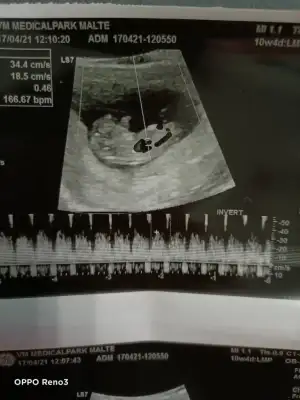

Kafasının hemen altındaki kordonu canim 😊 bana da erkek gibi geldi sanki ultrasonda seyredince pipisi dik gibi geldi ama bakalım yazicam sana tekrardan .çok sağol canım .2hafta sonra Dr tahmin etmezse yyeni foto atarım .

Merhaba benim ultrasonuma da bakar mısınız 12+2 😌